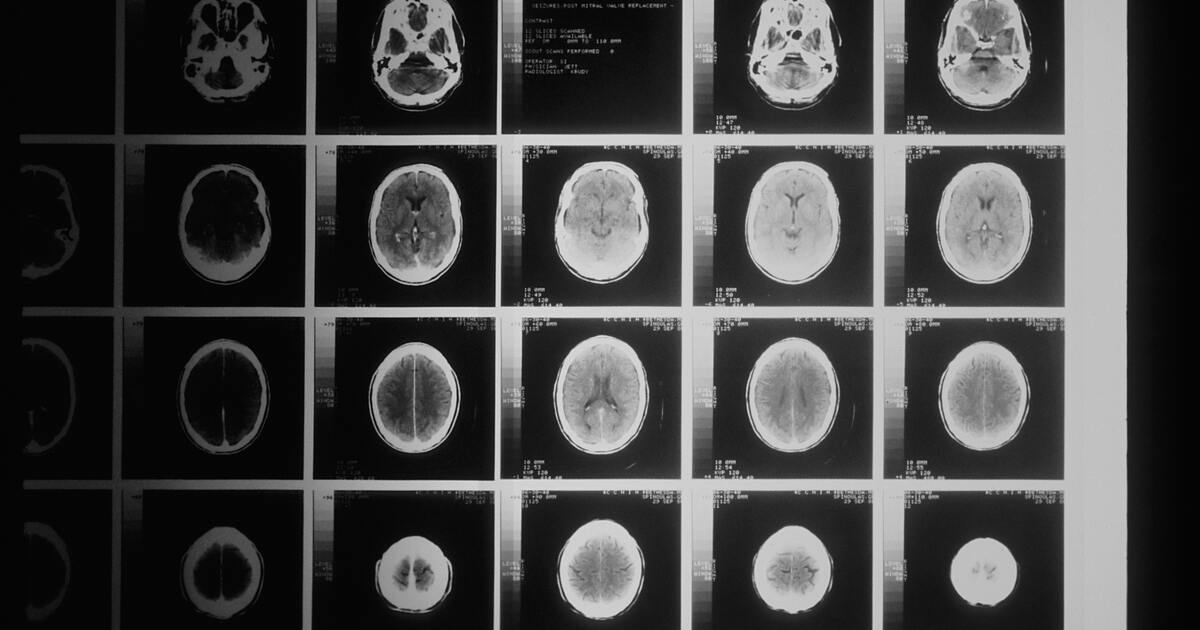

Учёные заявили, что сейчас всё больше осознают: депрессия вызвана нарушенными нейронными цепями. Исследователи увидели характер мозговой активности, возникающей при обострении симптомов депрессии у Сары. На основе этого они определили цель стимуляции.